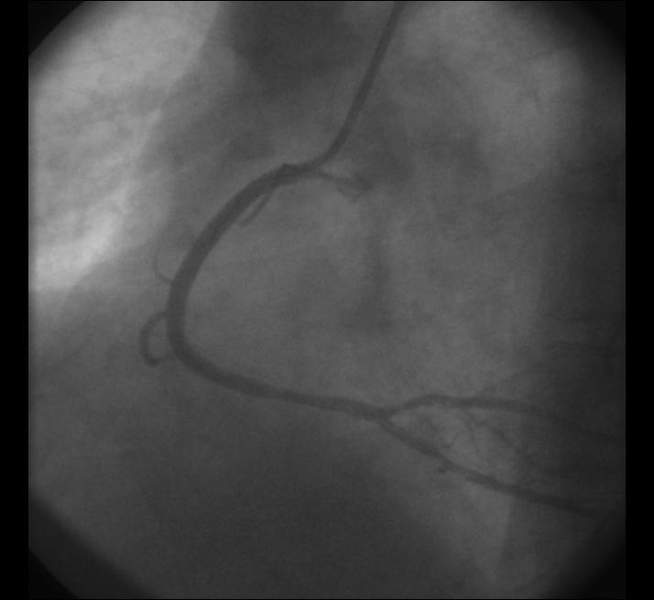

Das Herzkatheterlabor, das zur Behandlung von Notfällen rund um die Uhr besetzt ist, besteht aus zwei Herzkatheter-Messplätzen, so genannten Koronarangiographieplätzen. Hier werden jährlich rund 2000 diagnostische Untersuchungen und gut 950 Dehnungen der Herzkranzgefäße durchgeführt.

Bei dieser Untersuchung wird das linke Herz über eine Schlagader sondiert. In den meisten Fällen benutzen wir hierzu die Handschlagader.

Coronarangiographie und PTCA von der Arteria radialis (Handgelenk)